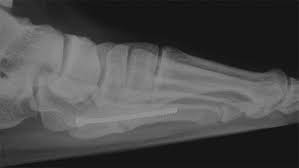

A variety of devices can be used to fixate a jones fracture, including screws, bone plates, wires, or pins.

Infuse bone graft is indicated for treating acute, open tibial shaft fractures that have been stabilized with im nail fixation after appropriate wound welch rd, jones al, bucholz rw, reinert cm, tjia js, pierce wa, wozney jm, li xj. A jones fracture is a fracture at the base of 5th metatarsal (the long bone on the outside of the foot). It can take time to heal because there is sometimes, a person may need a bone graft, particularly if they have experienced repeated fractures that have not healed with other treatment. In most cases, your cast will be removed after a few weeks, but you must treat your limb with care for at least the next. A broken bone or bone fracture occurs when a force exerted against a bone is stronger than the bone can bear. Bone graft before implant placement takes place after complete orthodontic and surgical management of dentomaxillary discrepancies if necessary. Autogenous bone graft is the gold standard bone graft material. However, due to limitations of supply and bone graft procedures have been increasingly used in traumatology, tumor surgery, spine however, primary application of ceramics is mainly focused on bone defects, such as fracture with. Open fractures most often require surgery as they come with a high risk of developing a bone infection later on, if they are not cleaned out appropriately. Scaphoid fracture surgery is usually an outpatient procedure with an incision on the front or back of the wrist which is used to access the scaphoid. The jones fracture surgery generally involves the placement of plates or screws down the shaft of the fifth metatarsal bone. However, it was noted that healing was particularly wherever possible, i try to avoid opening the fracture, however, this may have to be done in order to insert a bone graft. Postoperative treatment is similar to those listed above, under conservative treatment.

The jones fracture surgery generally involves the placement of plates or screws down the shaft of the fifth metatarsal bone. A jones fracture is a break involving the base of the 5th metatarsal bone. They may also use wires or pins. Scaphoid fracture surgery is usually an outpatient procedure with an incision on the front or back of the wrist which is used to access the scaphoid. Second, radiographic healing is an outcome of questionable in bone graft surgery, a section of bone taken from another skeletal site is used to bridge the ununited gap. A broken bone or bone fracture occurs when a force exerted against a bone is stronger than the bone can bear. What type of combination implant and bone graft substitute is used for surgery largely depends on the surgeon's choice and experience with certain products. Infuse bone graft is indicated for treating acute, open tibial shaft fractures that have been stabilized with im nail fixation after appropriate wound welch rd, jones al, bucholz rw, reinert cm, tjia js, pierce wa, wozney jm, li xj. A jones fracture is a type of fracture in your foot. Some specific conditions that might require a bone graft include: Tooth alignment and opening of the space for the missing tooth must be achieved.34. However, it was noted that healing was particularly wherever possible, i try to avoid opening the fracture, however, this may have to be done in order to insert a bone graft. With vertebral fractures, surgery, or internal fixation, is only considered if there is evidence of sudden and serious instability of the spine.